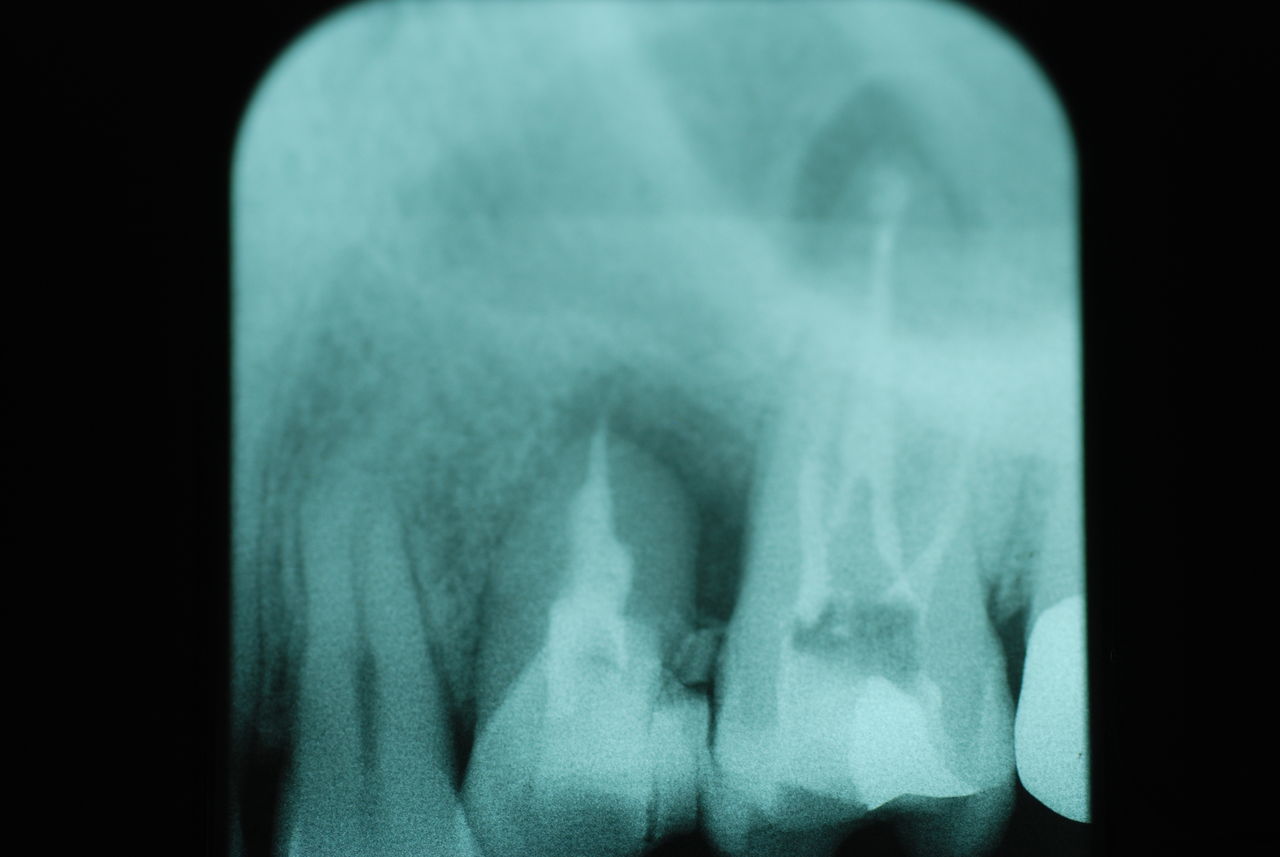

相談しても“問題無い”の説明だけだそうです。調べたところ歯周病は進行しているし、奥歯の大きい歯2本ずつ計4本はしっかり噛んでいないのです。よく噛めないというのはそのことのようでした。これを矯正的に元に戻すことはできない訳ではありませんが、時間と手間がかかるのは間違いないことです。

歯を削らないといいましても結局歯の間を削りスペースを確保したそうですから、何らかの歯に対する傷害はしているのです。それは虫歯や歯周病を起こしやすい理由にもなりますからこれからも要注意なのです。二年間という貴重な時間を費やしていますから患者本人は大変だったと思います。そして二年間を要したならば更に二年間動かないようにするための入れ歯やマウスピースを装着し続けなければいけないのです。